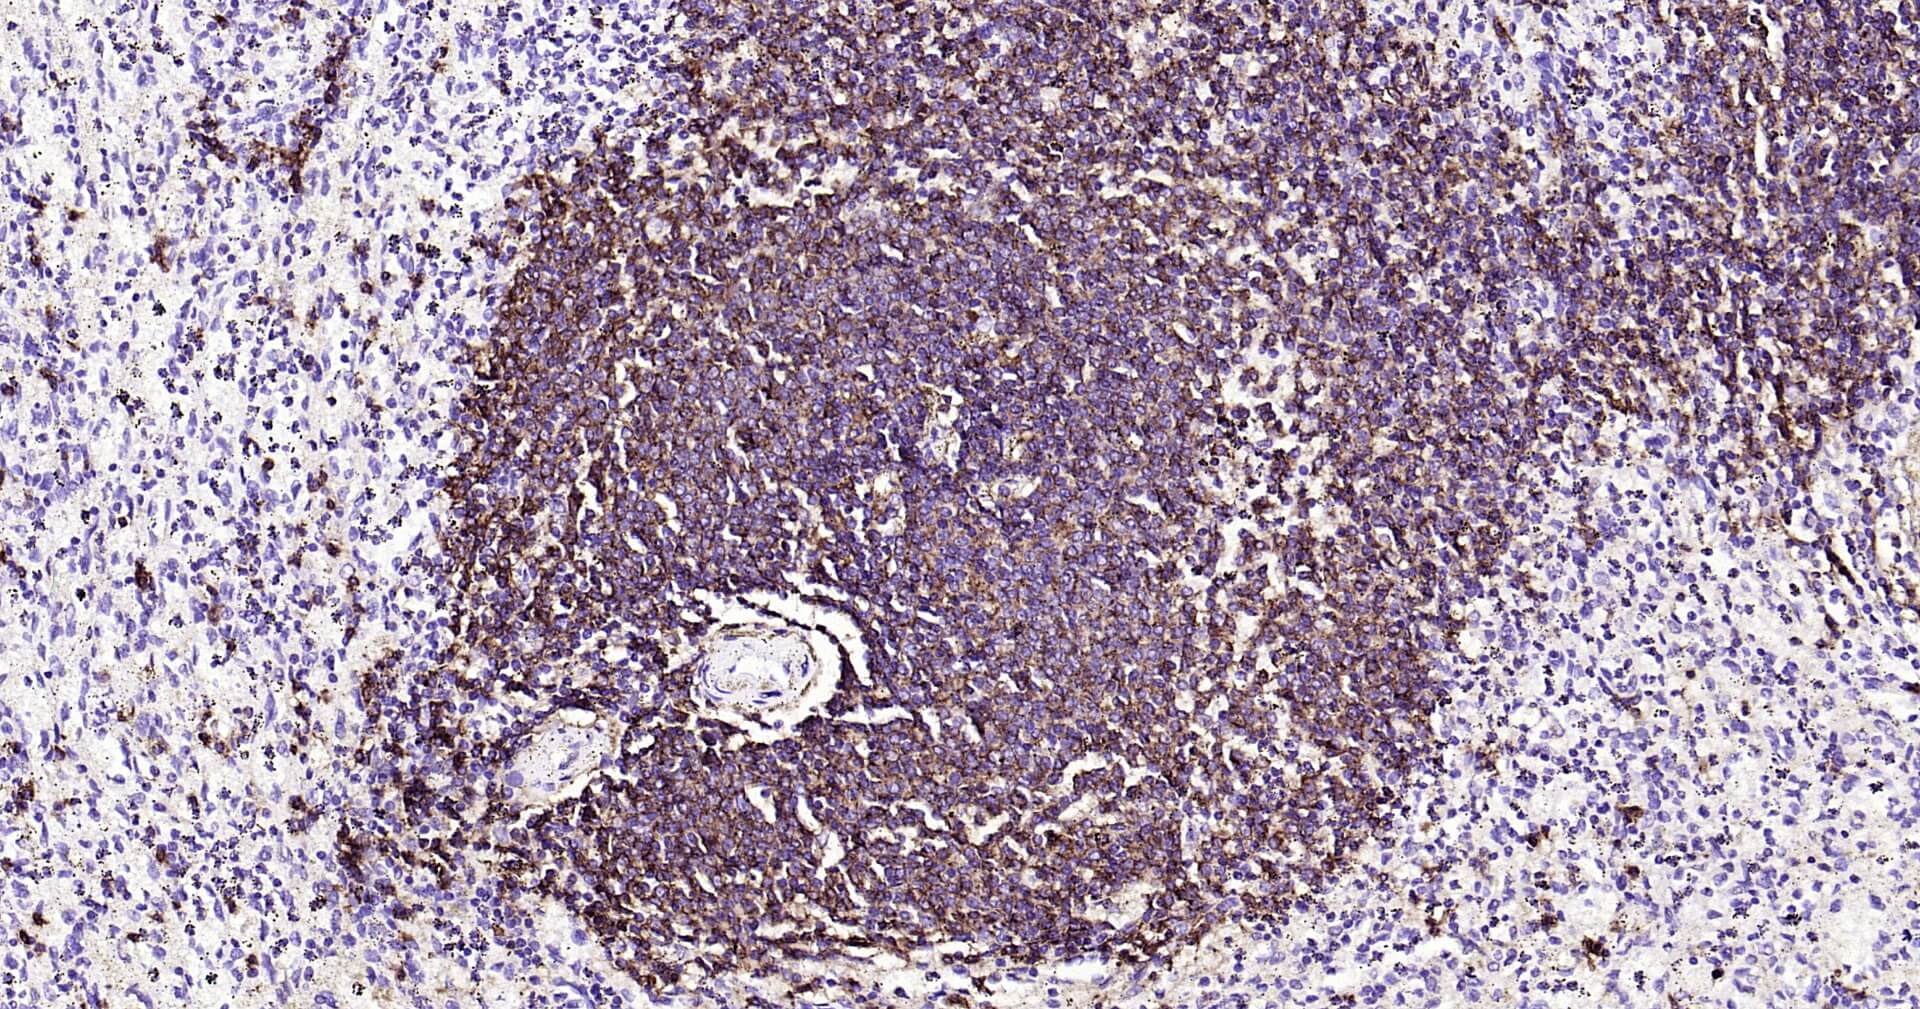

Immunohistochemical analysis of paraffin embedded mouse spleen tissue slide using IHC0125 (CD20 IHC Kit).

Immunohistochemical analysis of paraffin embedded rat spleen tissue slide using IHC0125 (CD20 IHC Kit).

Immunohistochemical analysis of paraffin embedded human spleen tissue slide using IHC0125 (CD20 IHC Kit).

Immunohistochemical analysis of paraffin embedded human tonsil tissue slide using IHC0125 (CD20 IHC Kit).